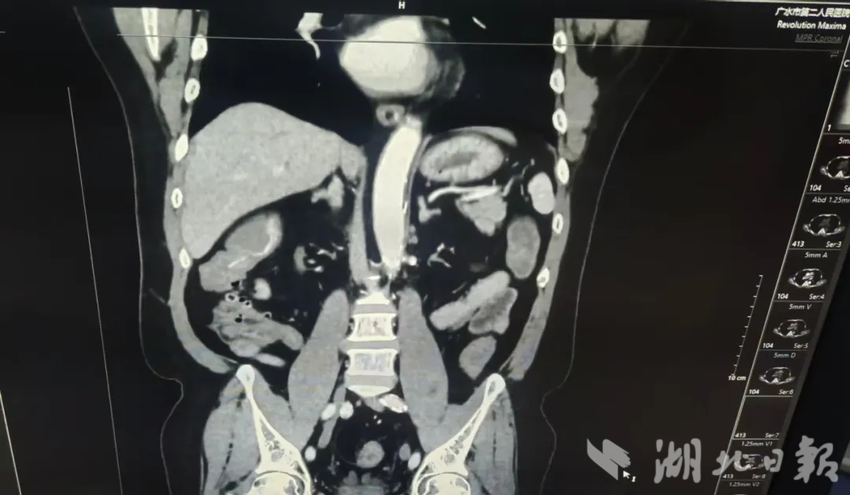

对于胃肠道大出血患者而言,时间就是生命。腹部增强CT,正是这场与死神赛跑中的关键“导航仪”。接令后,放射科技师与护士火速行动,十分钟内便完成机器启动、对比剂配置等所有准备工作。患者抵达科室的瞬间,检查立即展开。扫描结束,原始影像实时传输至诊断工作站,科主任迅速阅片分析,凭借丰富的临床经验和精准的影像解读能力,很快得出明确诊断:“动脉期升结肠小结节样、条状明显强化影,多考虑小动脉显影;静脉期、延迟期升结肠见片状高密度影,考虑造影剂聚集,回盲部周围多发憩室。”一份清晰的急诊报告,为后续救治赢得了宝贵时间。

凌晨时分,患者按计划转往随州市中心医院接受进一步治疗。依托广水市第二人民医院提供的腹部增强CT报告,随州市中心医院精准锁定病灶位置,针对性开展急诊肠镜检查。检查结果与CT诊断完全吻合,医护人员借助CT定位信息,快速实施内镜下止血治疗,成功控制出血,一场跨城区的生命接力圆满完成。